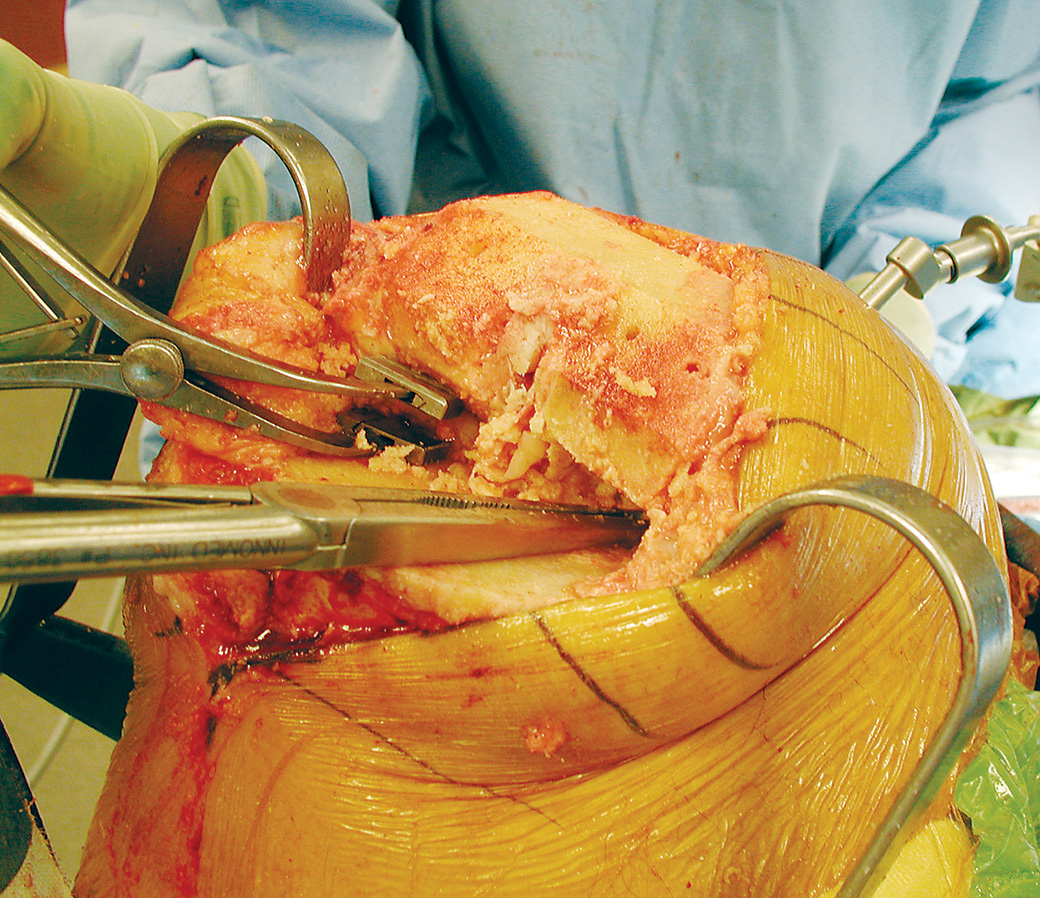

Femoral Tibial Spreader – Medium with Speed Lock and Grooved Pads

Speed lock modification designed by Nasim A. Rana, MD

Helps separate the femur and tibia during total knee replacement surgery

Speed lock helps allow precise control and prevent unintended release.

Designed to remain in position, with the femur and tibia separated, without the need of an assistant, and to minimize crushing the bone, even if osteoporotic. A wide unobstructed view of the posterior compartment is possible. Osteophytes on the posterior condyles of the femur and tibia can be seen and removed.